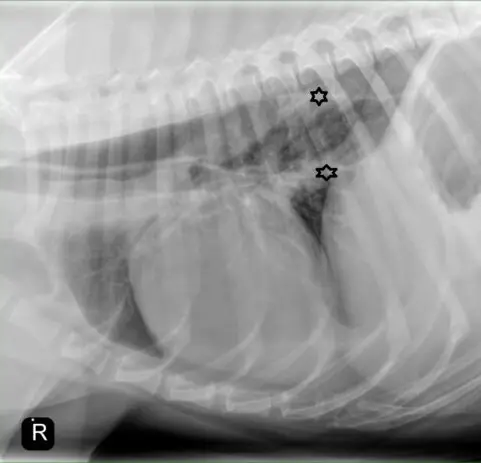

Megaesophagus xray

Above is a thoracic radiograph of a dog with Myasthenia Gravis and Secondary Megaesophagus. See the stars, which show the visible line of the esophagus; this line is typically not visible, and when it is visible it usually indicates dilation of the esophagus.